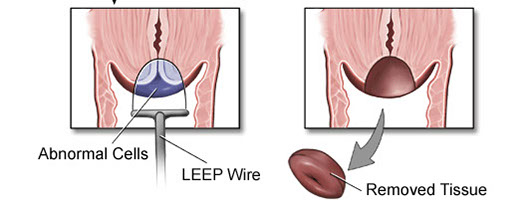

Grossing

Loop Electrocautery Excision Procedure (LEEP) or Large Loop Excision of the Transformation Zone (LLETZ)

1. Id endo and ectocervical margins

2. Ink ectocarvical margin and stroma with 1 color, the endocervical margin with another

3. If cylindrical, divide into halves and section longitudinally

4. If saucer-shaped, section radially

5. TE the specimen

Cone Biopsy

Similar as LEEP, orient c stitch at 12, inking the stroma and ectocervical margins 1 color and the endocervical another, then section radially as a cylindrical LEEP specimen, submitting in series around the clock in 3 hour intervals (12-3, 3-6,..9-12)

- TE specimen